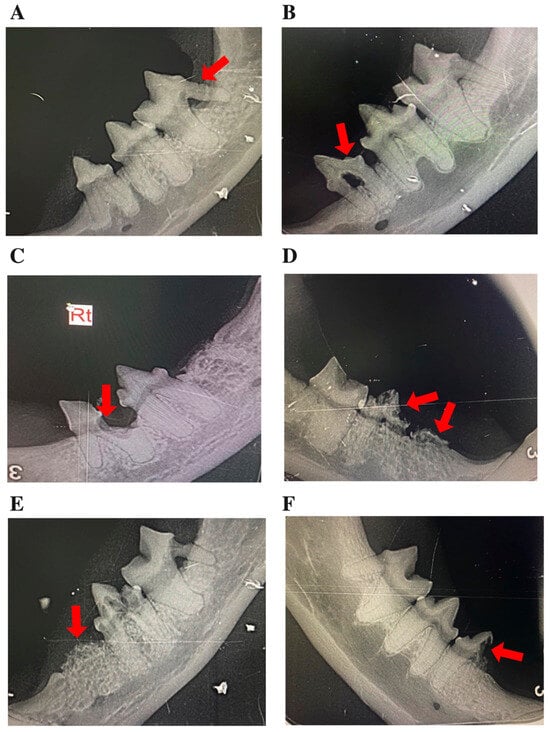

Data were retrieved from the hospital’s electronic medical record system, including demographic information (age, sex, breed) and dental findings. Full-mouth intraoral radiographs were obtained under general anesthesia using the PORT-X IV Portable X-ray system (Genoray, Seongnam-si, South Korea) and the CR 7 Vet Image Plate Scanner (iM3 Dental Limited, Duleek, Ireland), following standardized hospital protocols. Lesions were classified by type (1–3) and stage (1–5) according to AVDC criteria [11]. The location of affected teeth was recorded, distinguishing maxillary versus mandibular involvement and identifying the specific tooth group (incisor, canine, premolar, or molar). The presence of CGS was determined from clinical examination and intraoral inspection (Figure 1). Representative clinical and radiographic images of CGS, periodontal disease, and TR lesions at different stages are presented in Figure 2. All radiographs were independently reviewed by three trained clinicians, and any discrepancies were resolved by consensus. Formal inter-observer reliability testing was not performed and is acknowledged as a limitation. All evaluators followed standardized scoring criteria to ensure consistency and reduce variability in lesion classification.

Figure 2. Representative intraoral radiographs of mandibular premolars and molars in cats, depicting: (AE) tooth resorption (TR) stages 1–5, illustrating the progressive loss of dental hard tissue, as indicated by arrows; and (F) a mixed lesion exhibiting features of both Type 1 and Type 2 TR (arrow). In panel C, “Rt” denotes the right side.